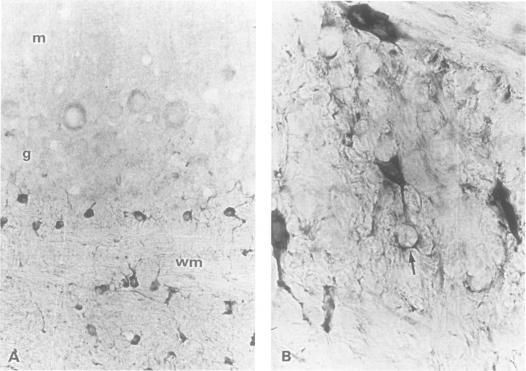

Of 45 patients with PNS whose serum was probed on paraformaldehyde fixed rat brain sections, 11 patients were identified whose serum samples recognised a cytoplasmic antigen in a subpopulation of glial cells in the white matter of adult rat brainstem, cerebellum, and spinal cord that were double labelled with a monoclonal antibody specific for oligodendrocytes. All serum samples reacted with a 66 kDa protein of newborn rat brain on western blot analysis. These antibodies were designated as anti-CV2 antibodies. Only one of the 11 patients had one of the well characterised autoantibodies (anti-Hu). Five patients had cerebellar degeneration, three had limbic encephalitis, two had encephalomyelitis, and one had Lambert-Eaton myasthenic syndrome. The tumours were small cell lung cancer or undifferentiated mediastinal cancer in seven patients, uterine sarcoma in two, and malignant thymoma in two. Among 1061 control serum samples, only two patients had anti-CV2 antibodies. One had small cell lung cancer and the other malignant thymoma.

在45例PNS患者中,用其血清检测经多聚甲醛固定的大鼠脑切片,发现11例患者的血清样本能识别成年大鼠脑干、小脑和脊髓白质中胶质细胞亚群的一种胞质抗原,这些胶质细胞用少突胶质细胞特异性单克隆抗体进行了双重标记。所有血清样本在蛋白质印迹分析中均与新生大鼠脑的一种66 kDa蛋白发生反应。这些抗体被命名为抗CV2抗体。11例患者中只有1例具有一种已明确的自身抗体(抗Hu)。5例患者有小脑变性,3例有边缘叶脑炎,2例有脑脊髓炎,1例有兰伯特-伊顿肌无力综合征。肿瘤在7例患者中为小细胞肺癌或未分化纵隔癌,2例为子宫肉瘤,2例为恶性胸腺瘤。在1061份对照血清样本中,只有2例患者有抗CV2抗体。1例患有小细胞肺癌,另1例患有恶性胸腺瘤。